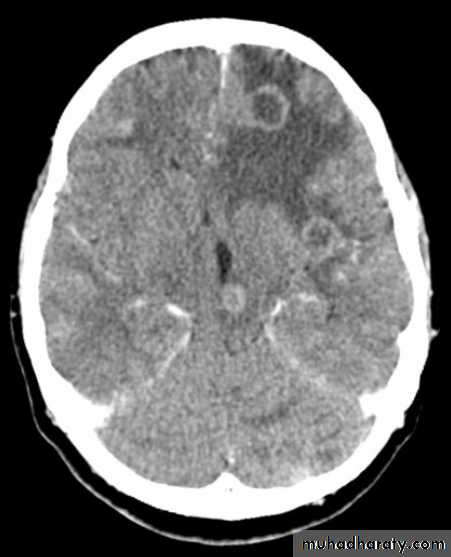

CT finding

meningioma presented as isodense area or slightly hyper density area with surrounded crescent of hypo density ( csf cap ) post contrast injection the lesion enhance homogeneously with enhancing Dural tail .

20 % show calcification

hyperostosis & thickening of the near by bony part of the skull & diplioc space .

it may be associated with little or no peri focal edema .

if the lesion associated with central necrosis with large perifocal edema meningio sarcoma should be excluded .